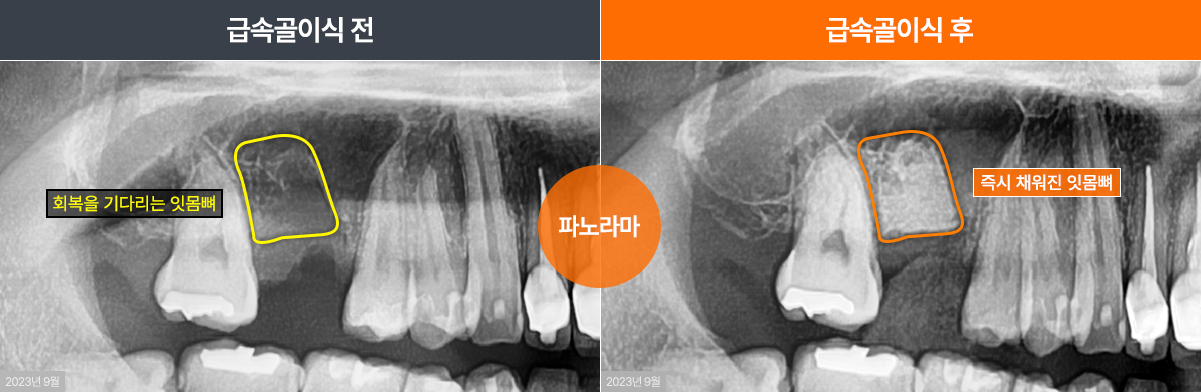

발치 후 방치시 잇몸뼈 수축 예상

급속골이식을 통해 충분한 잇몸뼈 확보

발치즉시 급속골이식을 통해 상악동의 함기화가 생기지 않아 상악동거상술 없이 튼튼한 치조골 확보

급속 골이식을 통해 12mm 충분한 두께의 잇몸뼈 확보